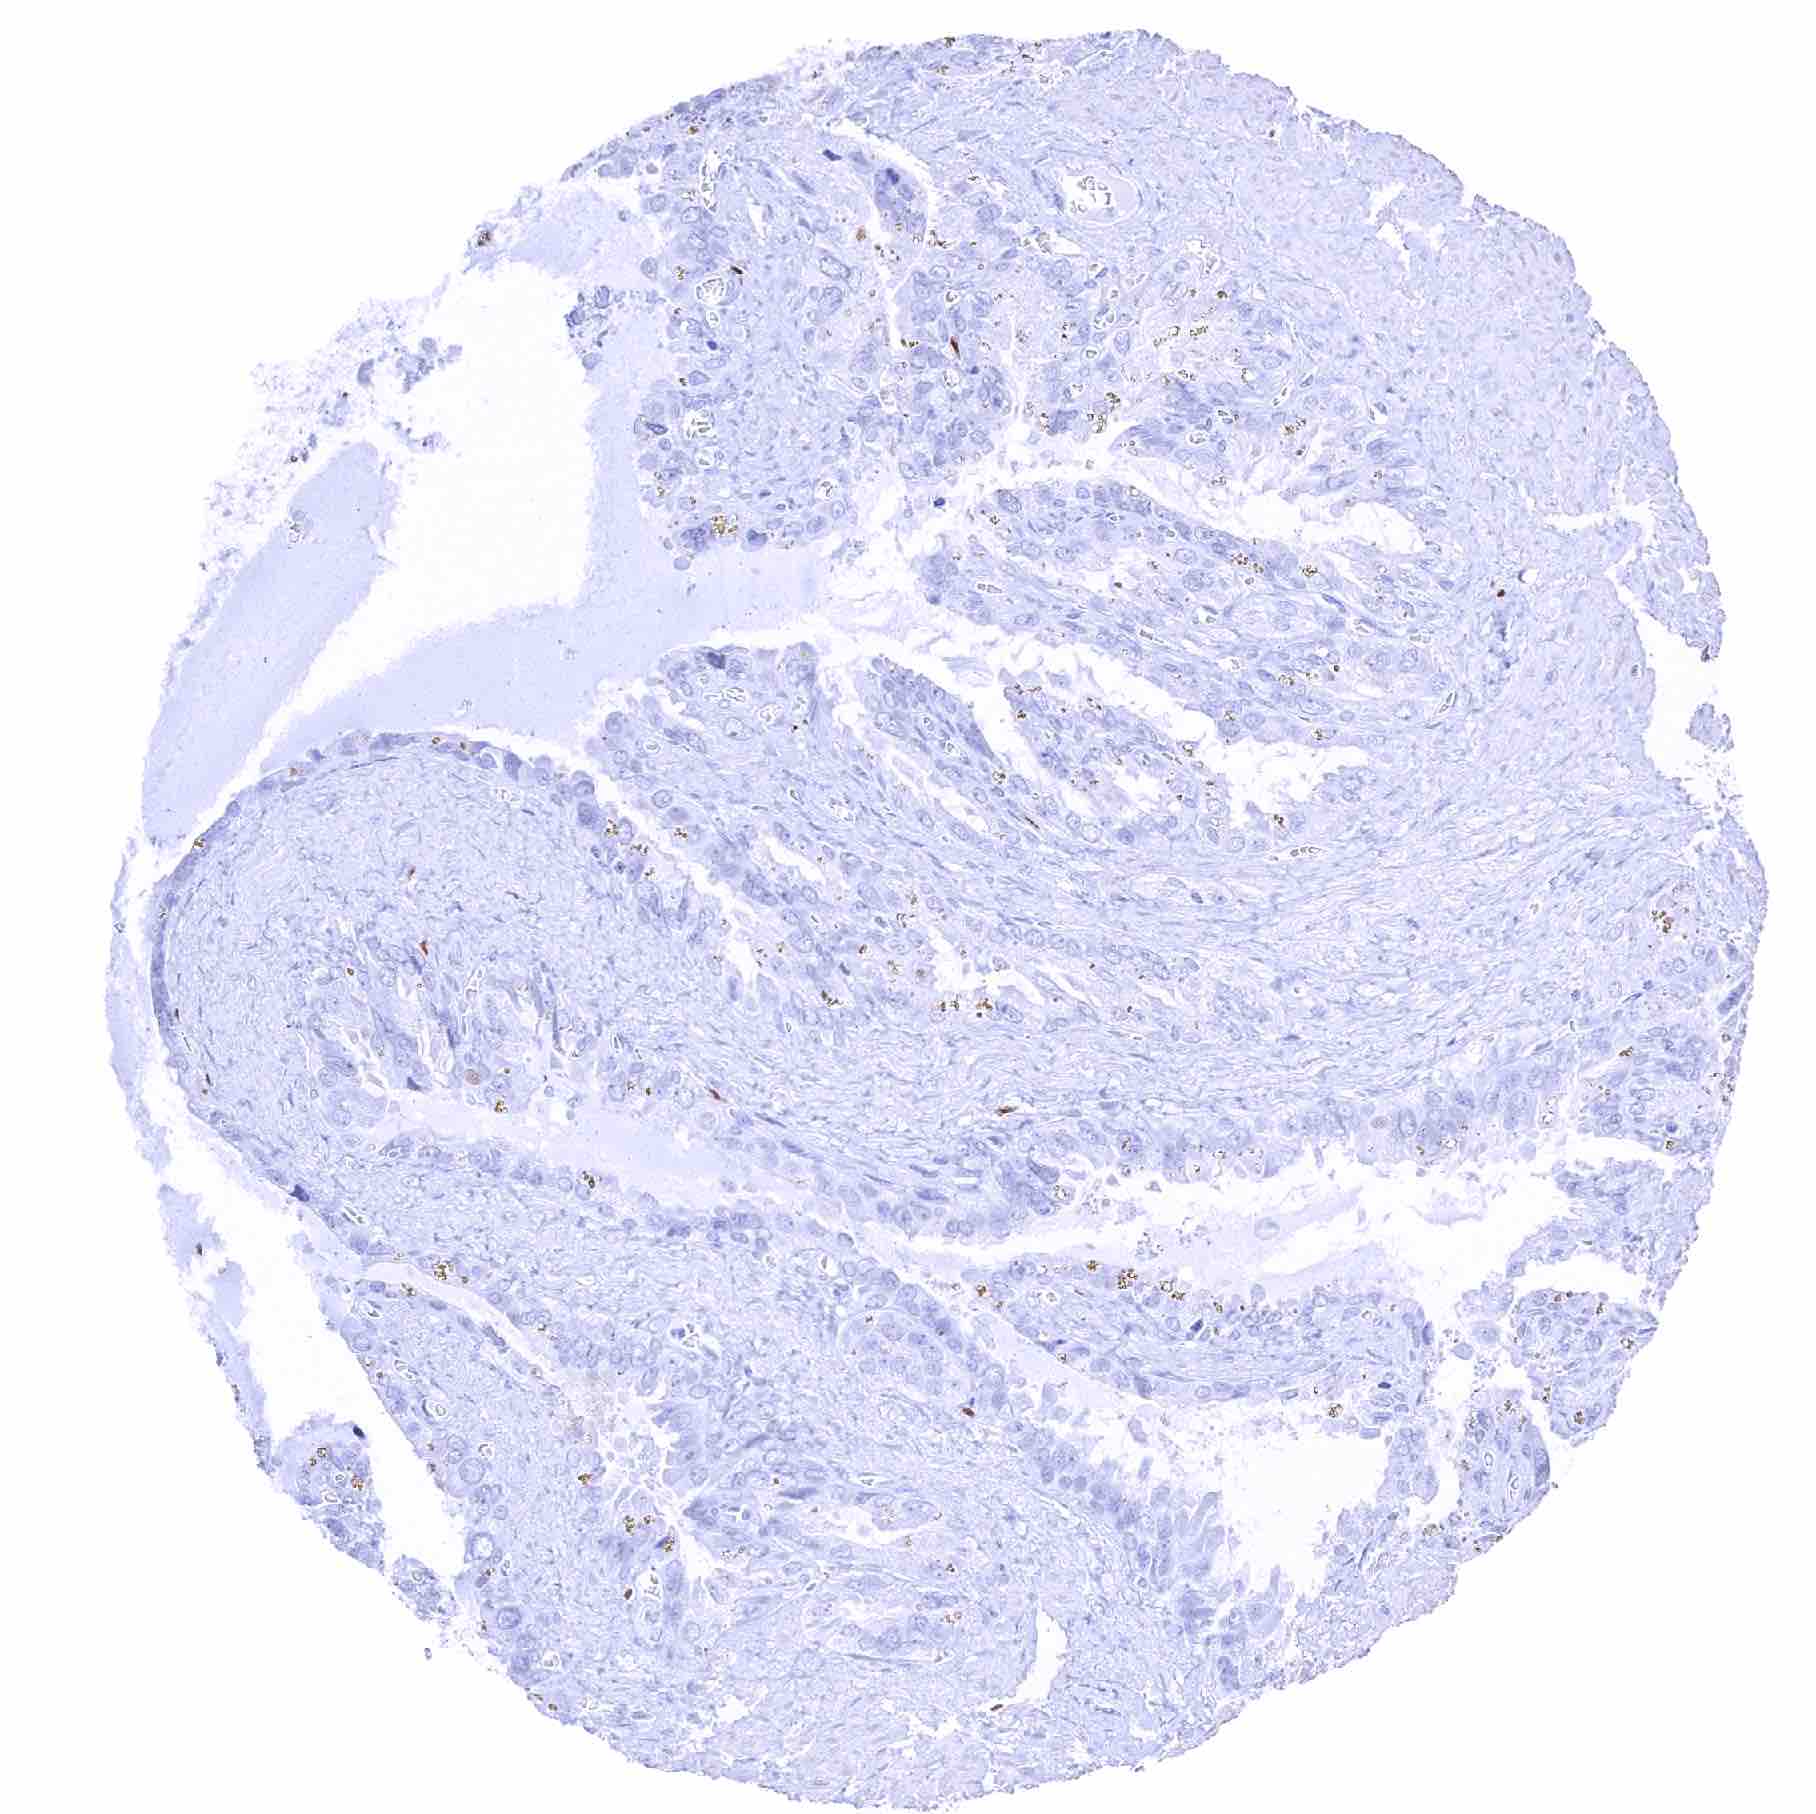

Uterus, endocervix – Weak to moderate SOX2 positivity of endocervical cells

Uterus, endocervix – Endocervical cells are SOX2 negative in this sample